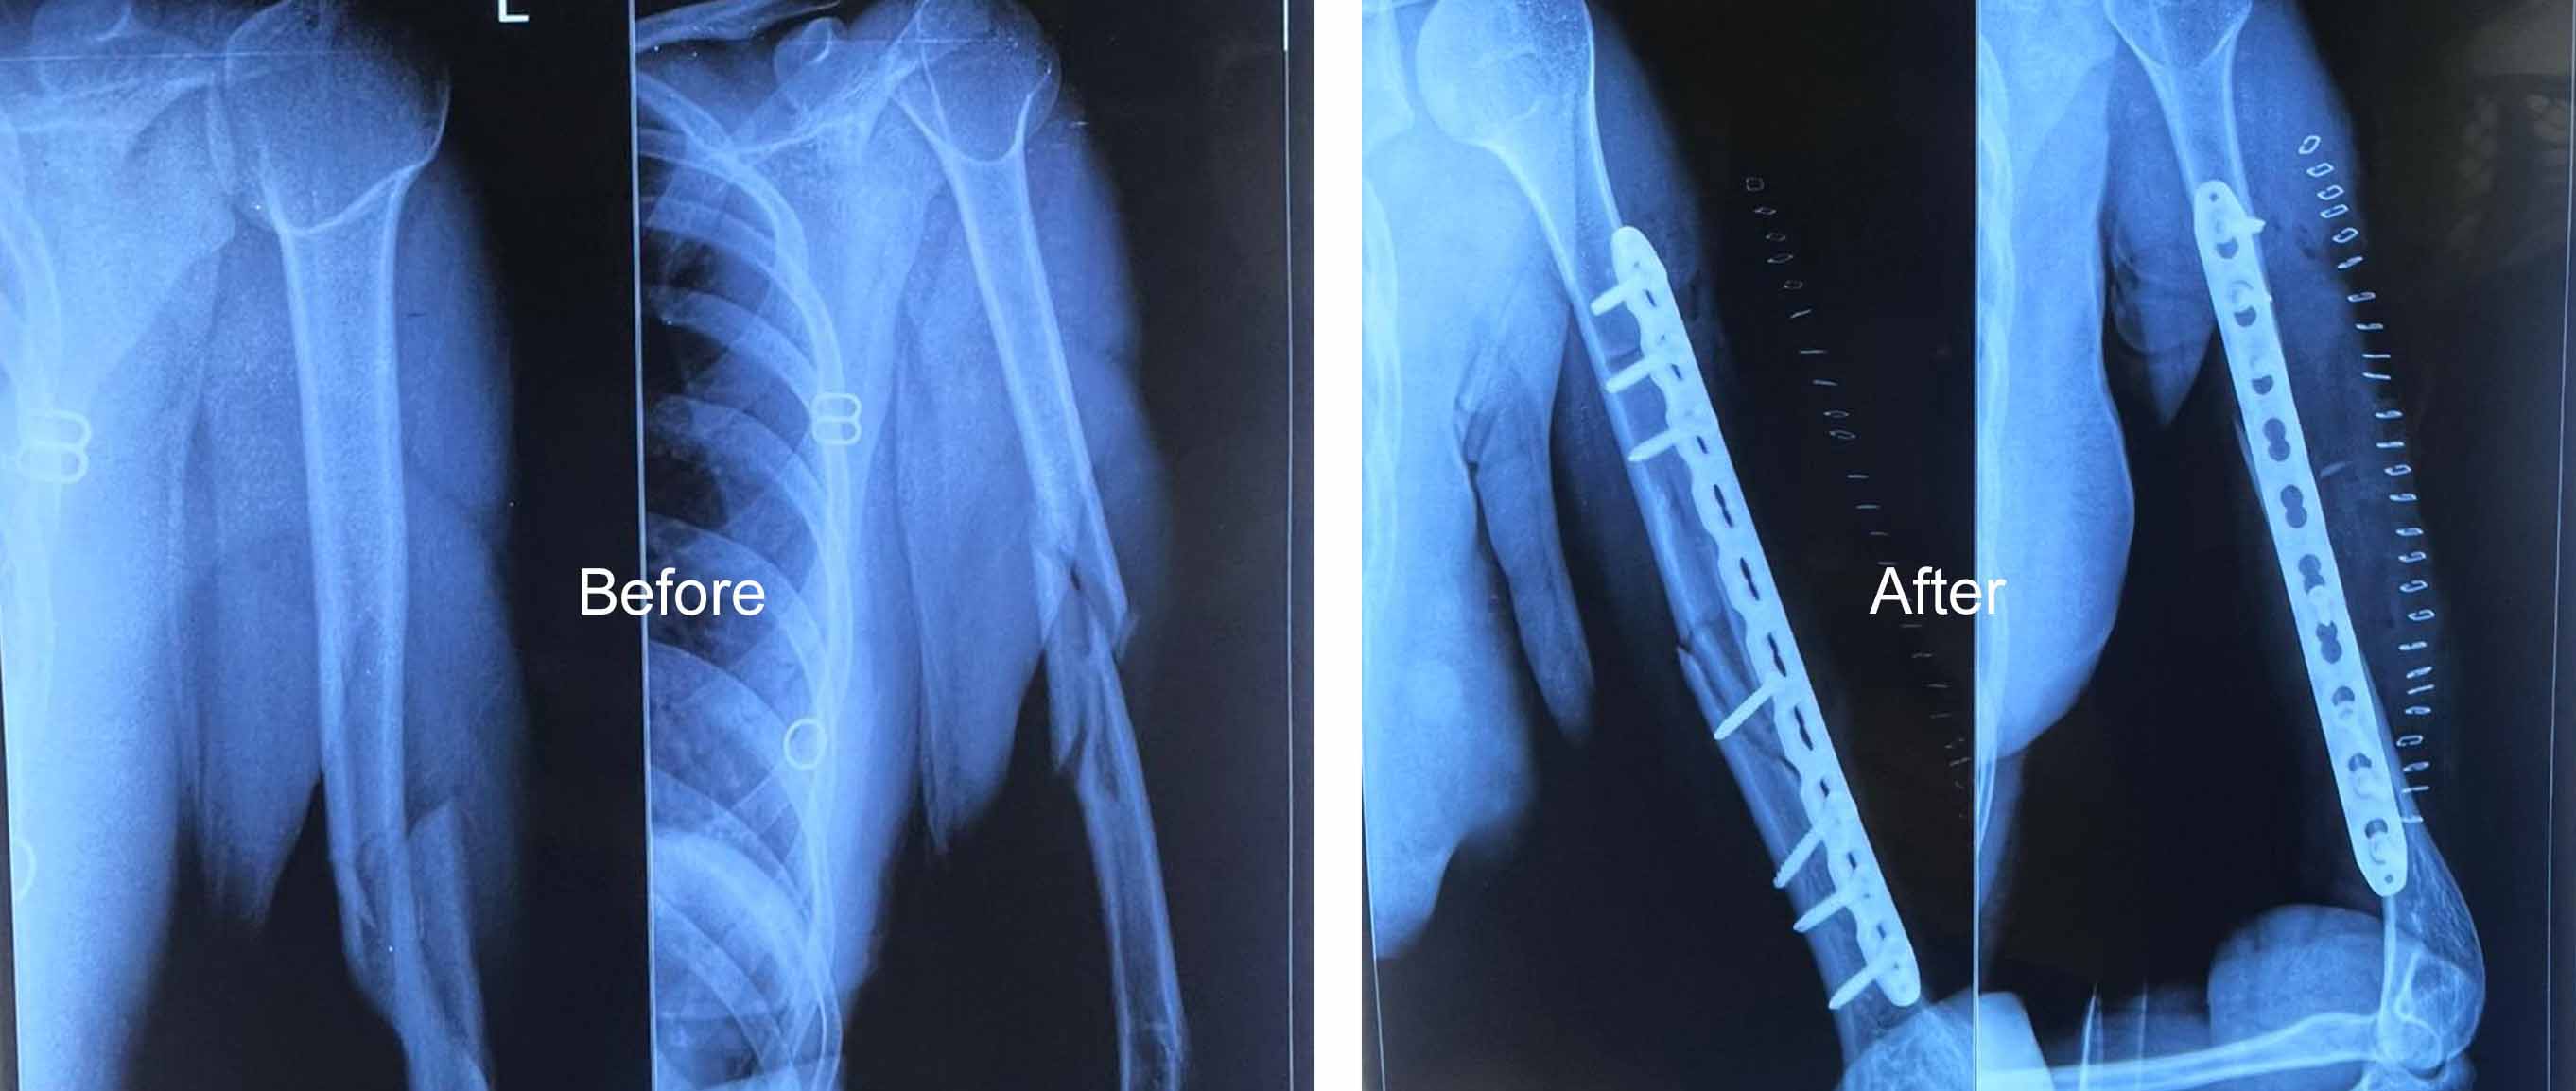

Orthopedic Care